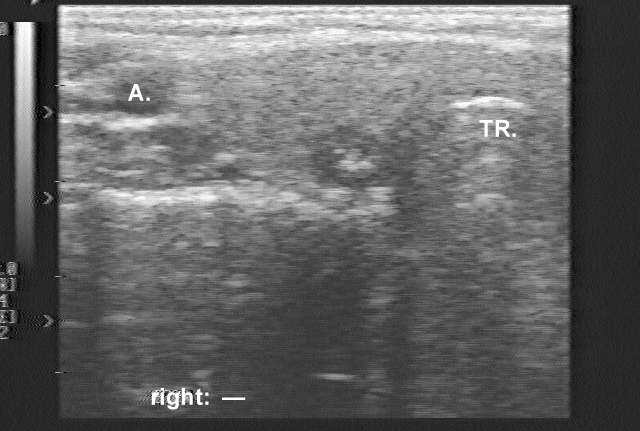

Ultrasonography revealed an 8 mm hypoechogenic nodule with one coarse hyperechogenic granule without dorsal acoustic shadow. (The patient was evaluated in 1995, therefore the sonographic images are technically out of date. Nevertheless, these are still edifying.)

1. The sonographic pattern is very specific for medullary cancer: cotton-like hyperechogenic patches without acoustic shadow occupying more than 50% of a hypoechogenic nodule.